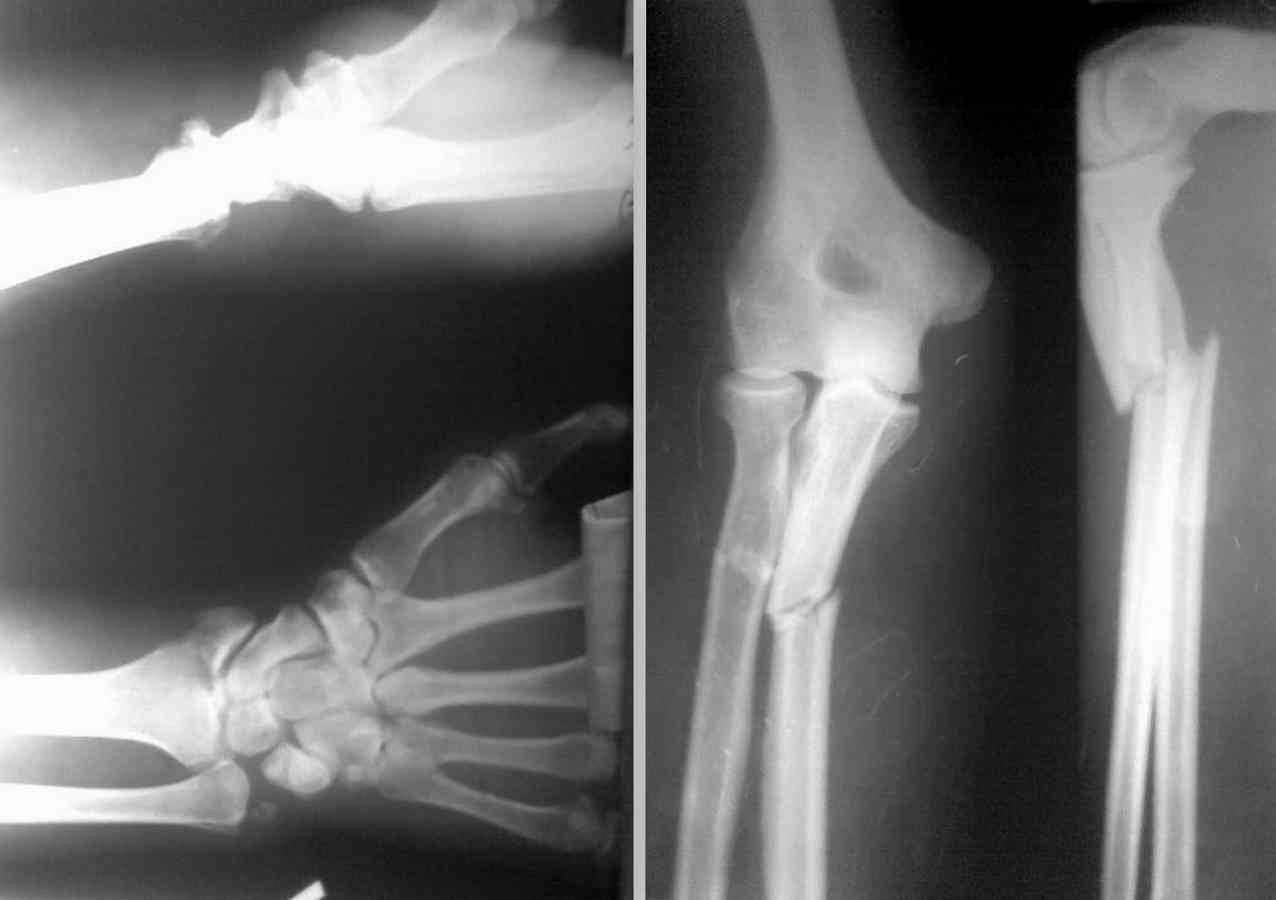

Добрый день,коллеги. Поступил больной 30 лет после падения с высоты 1,5 м.на ладонь. Травма 8 суток назад, в поле моего зрения попал только сегодня.

Неврологии нет. Со слов отмечался выраженный отёк предплечь,кисти и пальцев. В настоящее время отёк умеренный, движения пальцев кисти сохранены.Проблем с синтезом локтевой кости не вижу.

Имеются вопросы по лучевой, а именно:

Собственный план: Из тыльного доступа фиксировать проксимальный перелом луча пластиной типа LCP (короткий проксимальный фрагмент)Дистальный перелом фиксировать из тыльного(?) доступа винтом или может быть Ex-fix?

Локоть вопросов не вызывает - 3.5 мм компрессионная пластина по АО доступ - тыльный, локоть лежит прямо под кожей.

проксимальный фрагмент луча короткий, я бы потому передним доступом Генри пластину поменьше и поуже - треть-трубчатую на 4 отверстия или что-нибудь под 2 мм шурупы. Можно было бы и блокированный гвоздь, но вот что делать с переломом дистального луча? вводить гвоздь фактически через перелом? я бы не стал

Отправитель: Adonin 31 Октябрь 2010, 02:13

Подчеркну - ПЕРЕДНИЙ ( ладонный) доступ на проксимальный перелом луча. при заднем ( Томпсоновском) доступе на уровне перелома столкнетесь с задним межкостным нервом, проходящем перпендикулярно волокнам супинатора- сложно идентифицировать и выделять, при травме получите паралич разгибателей.

Андрей Волна 31 Октябрь 2010, 08:55

Уважаемые коллеги, действительно, мне так же кажется, что перелом дистального луча здесь неполный внутрисуставной и без импрессии. Но у нас в больнице мы бы сделали КТ лучезапястного сустава дабы исключить неприятные неожиданности. Нет КТ - несколько косых проекций лучезапястного сустава выполнят схожую работу.

Начало, естественно, сверху - с какой кости - не столь принципиально. Мой выбор - с лучевой, тк репозиция в условиях уже зафиксированной локтевой будет, наверное посложнее, чего не хочется в этой деликатной зоне. Доступ - однозначно передний, о чём подробно пишет др Адонин. Пластина - я бы взял и реконструктивные под 3,5 мм и под винты 2мм и 1/3 трубчатую - но это не лучший выбор в данной ситуации, но в запасе бы имел. Для локтевой - всё стандартно, см у др. Адонина. Если подтверждается предположение о простом характере перелома дистального луча - попытался бы отрепонировать и фиксировать винтами малоинвазивно под ЭОПом. Нет ЭОПа - перед окончательным принятием решения после выполнения первой части операции на проксимальном отделе предплечья сделал бы Рконтроль в операционной лучезапясного сутава, тк положение отломков может существенно измениться после восстановления длины костей. При необходимости открытой репозиции внутрисуставного перелома (импрессия, невозможность малоинвазивной репозиции, полный характер перелома - типа С) я бы предпочёл всё же передний волярный доступ, как технически более простой, а винты ввёл бы при необходимоти через проколы кожи. С уважением, Андрей Волна

при взгляде на снимки дистального отдела предплечья хочется отметить значительный непорядок в "луче-локтевом" угле.